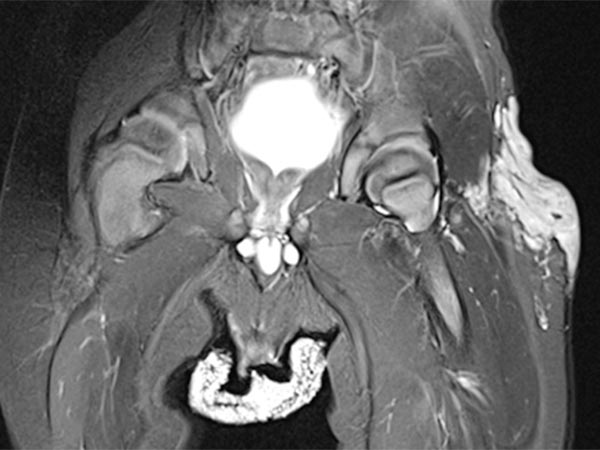

Coronal T2-weighted, fat-saturated MRI shows the tumor in the left groin as homogeneous and highly hyperintense (13 months of age) and clearly solid. Incidental findings include the soaked diaper, also with high signal intensity.

Same MRI sequence, coronal slice. The tumor is not only epifascial, but also shows a small subfascial extension under the fascia lata into the gluteal muscles. Thus, clearly infiltrative behavior.